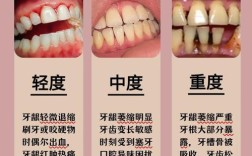

正常情况下,天然牙的牙根会持续刺激牙槽骨,维持其骨量,但一旦牙齿缺失,牙槽骨会因失去“功能性刺激”而逐渐萎缩——就像长期不运动的肌肉会萎缩一样,缺牙时间越长、年龄越大,牙槽骨流失可能越严重,表现为骨宽度不足(<8mm)、骨高度不足(<10mm)或骨密度疏松,这确实是种植牙的一大挑战,但绝非“死结”。